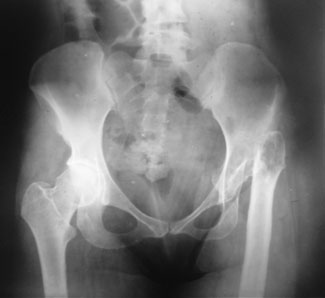

Before Surgery

As a result of infection and surgeries in childhood this 27 year old girl had destruction of the femoral head. As a result of that she had a very bad limp and shortening of the left leg. She also had a hyper-extension deformity at the proximal tibia (the knee would go back every time she would walk) and fixed equinus deformity of the ankle due to long standing shortening. An Ilizarov Hip Reconstruction was done for the left hip and in the 2nd stage the deformity in the knee & equinus were tackled.